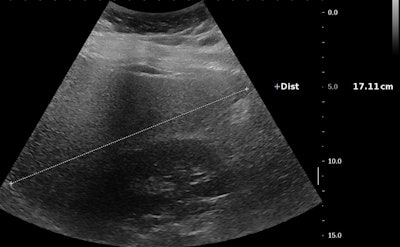

![Ultrasound of a 14-year-old girl with severe obesity (body mass index [BMI], 42 kg/m2). There is hepatomegaly associated with increased liver echogenicity when compared to the right kidney and attenuation corresponding to severe steatosis. Below, the same patient shows increased liver-to-kidney ratio. All images courtesy of Dr. Stéphanie Franchi-Abella, PhD.](https://img.auntminnieeurope.com/files/base/smg/all/image/2019/10/ame.2019_10_10_21_09_1189_steatose-fig-1a.png?auto=format%2Ccompress&fit=max&q=70&w=400)

Early detection is important, as diet may reverse the process at the early phase of the disease. Yet the detection and quantification of liver fat content and associated fibrosis and inflammation, mandatory in the diagnosis of NASH, remain challenging in children; B-mode ultrasound remains relatively limited for the diagnosis of liver steatosis, as fat content should be more than 20%, but quantification is not yet available as a routine clinical tool on ultrasound scanners, according to Franchi-Abella.